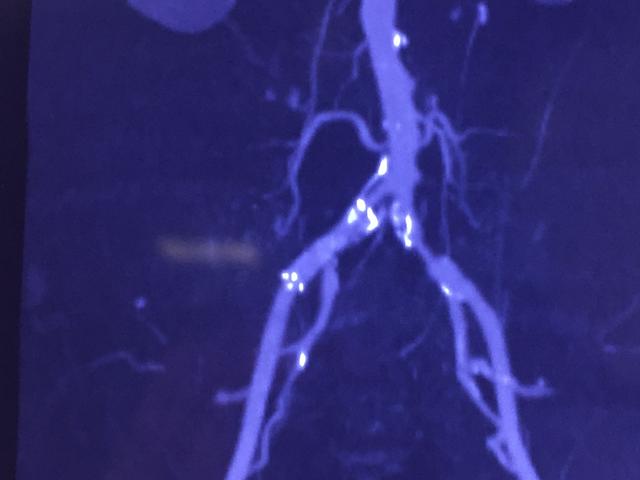

血管外科经常收治一些病人是因为“肾虚”而来的,他们的主要表现是:腰酸腿痛、下肢发凉伴乏力、臀部麻木、性功能障碍等等。这些表现显然符合中医的肾虚,在临床上更容易与腰椎病、偏瘫、髂关节及膝关节病鉴别不清,由于血管病变多见于中老年,与上述疾病发病年龄相当,而且往往会同时伴发,导致长期误诊。

对于这些患者,尤其是孤立的下半身症状患者,一定要注意下肢股动脉、腘动脉、足背及胫后动脉搏动的情况。其次注意温度、皮毛脱落、肌肉萎缩等,另外,还要注意与运动的关系,血管病变类似于心绞痛,活动后出现困痛。

血管外科经常收治一些病人是因为“肾虚”而来的,他们的主要表现是:腰酸腿痛、下肢发凉伴乏力、臀部麻木、性功能障碍等等。这些表现显然符合中医的肾虚,在临床上更容易与腰椎病、偏瘫、髂关节及膝关节病鉴别不清,由于血管病变多见于中老年,与上述疾病发病年龄相当,而且往往会同时伴发,导致长期误诊。

对于这些患者,尤其是孤立的下半身症状患者,一定要注意下肢股动脉、腘动脉、足背及胫后动脉搏动的情况。其次注意温度、皮毛脱落、肌肉萎缩等,另外,还要注意与运动的关系,血管病变类似于心绞痛,活动后出现困痛。